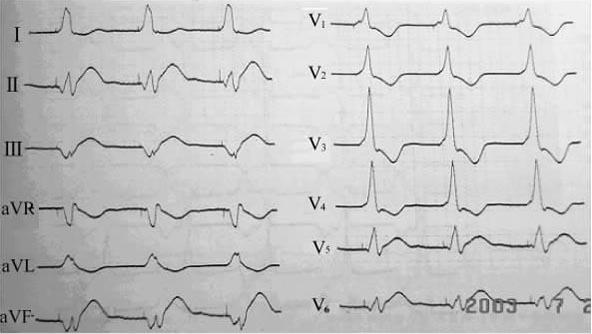

刺激信号代表脉冲发生器释出的脉冲电流,又称起搏信号或脉冲信号。体表心电图上的刺激信号表现为自基线上发生的一个陡直的电位偏转。刺激信号的时限很短而振幅差别很大。目前常用的脉冲发生器发放的脉冲刺激时限(脉宽)多在0.42ms左右,当以25mm/s的走纸速度记录体表心电图时,这个刺激信号表现为基线上的一条垂直线,故又被称为“钉样信号”。刺激信号的振幅与导线上两个电极之间的距离呈正比关系。因此,在单极起搏时,两个电极间相距较远,刺激信号常常较大,有时呈双相波形(可能由于较大的刺激信号回到等电位线时的“过冲现象”所致,图7-1-1)。而在双极起搏时,由于起搏电极间距近,刺激信号相对较小,某些导联体表心电图上甚至看不见。

图7-1-1 单极性起搏心电图:由于刺激信号过大,且发生过冲现象,使QRS波明显增宽变形

需要注意的是刺激振幅较大的起搏信号,其后的电位衰减指数曲线亦较大,两者可貌似正常的QRS波形。故此时应根据T波有无来判定是否存在真正的心室除极还是起搏脱漏(刺激信号后无心室除极波)。另需注意的是心电图上观察到的刺激信号方向,系由脉冲刺激的向量(自负极至正极)与心电图导联之间的关系所决定,故实际取决于埋藏式脉冲发生器在体内的位置。因此,不能以刺激信号的方向来判断起搏部位,而应通过观察起搏搏动的QRS波群形态和空间方位作出正确的定位和判断。

右心室心尖部通常作为右心室起搏的首选位置。由于右心室心尖部位于心脏前下方,该部位起搏时,心室除极方向为从心尖部向心底部,且右心室激动早于左心室,故体表心电图呈完全性左束支阻滞(CLBBB)图形,常伴以额面QRS电轴显着左偏(LAD,-30°~-90°)。因此,右心室心尖部起搏图形=LBBB+LAD。右心室心尖部起搏时,约一半患者V5、V6导联QRS波主波向上(图712)。另一半患者V5、V6导联QRS波主波向下或以S波为主(图713),说明心室除极的后半部分是自前向后的。

图7-1-2 右心室心尖部起搏心电图,起搏的QRS波呈LBBB+LAD,V5、V6导联QRS波主波向上

图7-1-3 右心室心尖部起搏心电图,起搏的QRS波呈LBBB+LAD,V5、V6导联QRS波主波向下